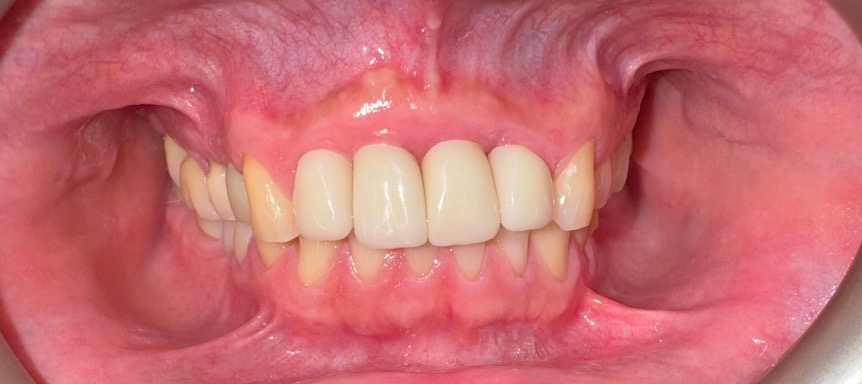

March 29, 2025Delivery of final anterior restorations on the four implants, restoring function, phonetics, and esthetics in the maxillary front region.

Ivan’s maxillary anterior region was restored from failing, unrestorable teeth to a stable, implant-supported reconstruction. The guided bone regeneration created sufficient bone volume for ideal implant placement, and soft tissue management allowed for a natural, harmonious smile line.

Function, phonetics, and esthetics were significantly improved, and the final restorations blend seamlessly with Ivan’s facial features. This case demonstrates how a biological, staged approach to extraction, GBR, and implant placement can successfully rebuild the anterior maxilla after significant structural compromise.